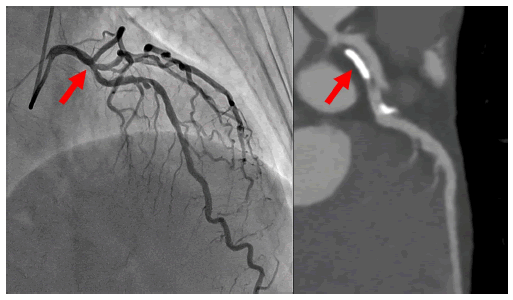

A 55-year-old man with a history of hypertension and smoking was evaluated for intermittent claudication, which revealed moderate stenosis of the proximal left anterior descending artery (Figure 1, red arrow). The lesion showed a significant reduction in fractional flow reserve (0.73, step-up 0.12), and a percutaneous coronary intervention was planned.

Figure 1: Coronary angiography and cardiac computed tomography of the left coronary artery. Moderate stenosis with eccentric calcified plaque can be observed in the proximal left anterior descending artery (red arrow).